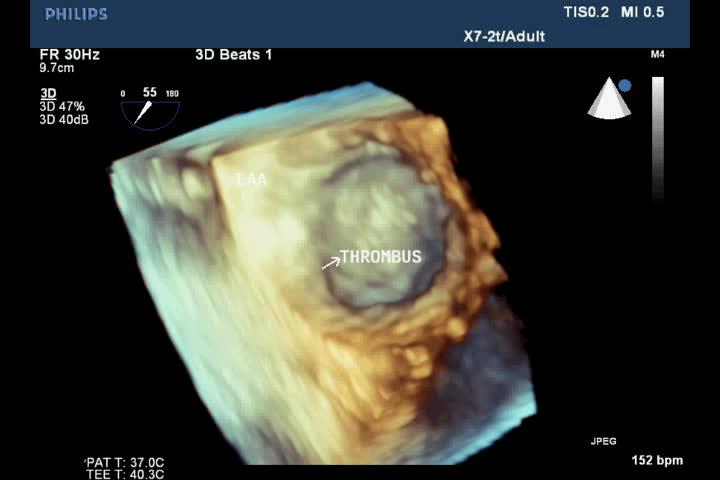

Figure 4. Thrombus in LAA on 3D TEE; “TEE image from Nguyen Tuan Vu”

TTE identifies the disease. TEE detects spontaneous contrast and thrombi in LA, LAA of patients with mitral stenosis. It is important to decide using anticoagulation before percutaneous balloon mitral valvuloplasty or surgery (Figures 1-8).

TTE can detect LA thrombus but the sensitivity is low. TEE is the credible technique to detect LA and LAA thrombi, with values of sensitivity and specificity about 99% [13].

TTE evaluates size and function of cardiac chambers, associated cardiac lesions such as valvular heart diseases, pericardial abnormalities. TEE evaluates size and morphology of LAA, velocity of LAA blood flow, identifies and excludes spontaneous contrast and thrombus of LAA and LA.